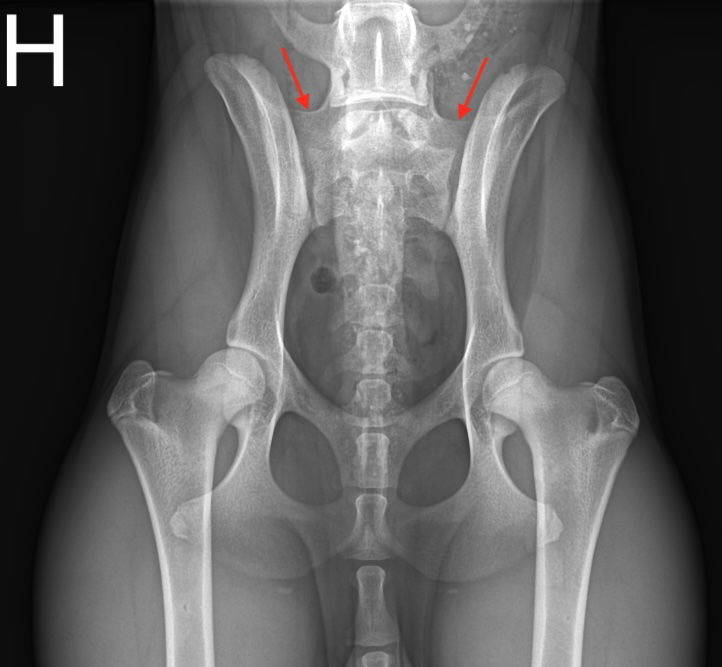

LTV2

Symmetrisk lumbosakral overgangsvirvel

LTV3

Asymmetrisk lumbosakral overgangsvirvel